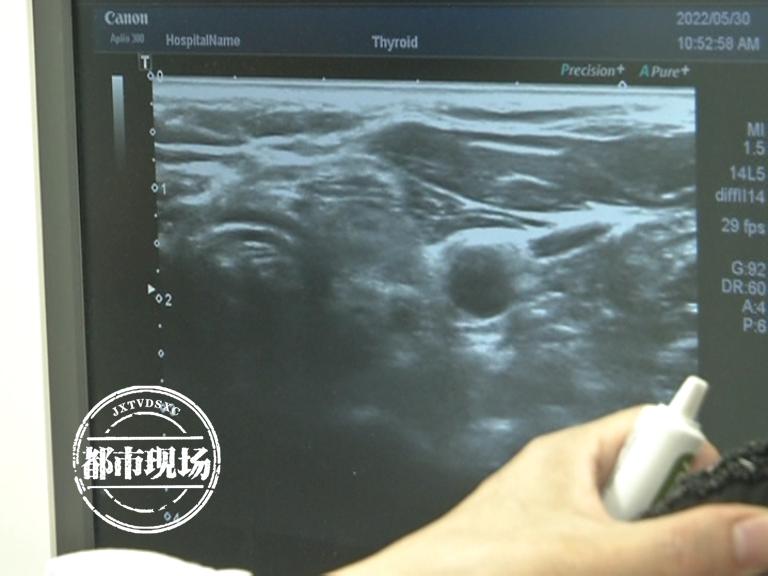

超声成像技术已逐渐成为医疗诊断的重要手手段之一,借助超声波在人体内的反射、散射等现象,我们能够获取人体内部结构和器官的图像,随着科技的进步,新型超声成像技术不断涌现,如三维超声、四维超声等高级成像技术,能够提供更详细、更准确的图像信息,超声弹性成像技术还能评估组织的硬度、弹性等物理特性,为医生提供更全面的诊断依据,这些新型超声成像技术具有无创、无痛、无辐射、便捷等特点,为医生提供实时、动态的诊断依据,大大提升了诊断的准确性和效率。